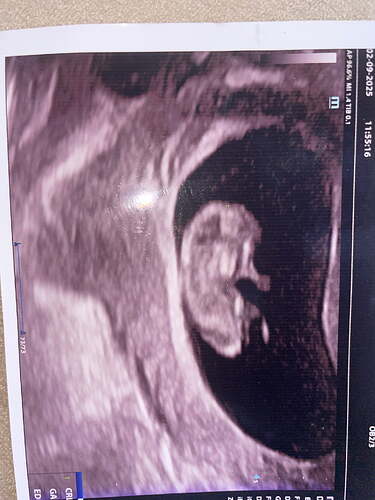

Anladgimdan değil ama erkek hissettim

bence erkek gibi

Erkek gibi

Erkek bebek kesesi gibi balım

Erkek gibii

galiba yuvarlak olanlar kiz yamuk yumuk sekilsizler erkek oluyo sizinki de erkek gibi

Büyük ihtimalle erkek canim

erkek gibi kesesi